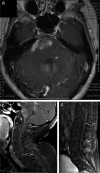

Results: 28 H3 K27M-mutant tumors were identified, with equal numbers of adults (13) vs. children (15). For adults, mean and median age was 52 years (range = 27 - 81 years), 2 decades older than a recently-published adult series. Tumors involved thalamic (adult = 7; pediatric = 7), spinal cord (adult = 4; pediatric = 2), pons (adult = 1; pediatric = 6), and hypothalamic (n = 1) sites. Other morphologies at presentation included pure GG (n = 3, pediatric) and PA (n = 1, adult). One adult and 1 pediatric patient each presented with leptomeningeal dissemination or developed leptomeningeal dissemination within 1 year after diagnosis, with transformation from PA or GG histology to glioblastoma. Mean survival was 9.3 (adults) vs. 8.9 (pediatric) months. Patients with tumors of other morphologies (GG, PA) did not enjoy extended survival.

Conclusion: H3 K27M-mutant tumors can affect patients at advanced ages, may show leptomeningeal dissemination at time of presentation, and "pure" GG or PA morphology is not rare. Regardless of patient age or tumor morphology, patients fare equally poorly. .